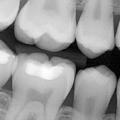

Odontotherapie

La carie dentaire, appelée le ver dentaire en antiquité, en absence de traitement, provoque des mals de dents, infection et même la perte des dents.